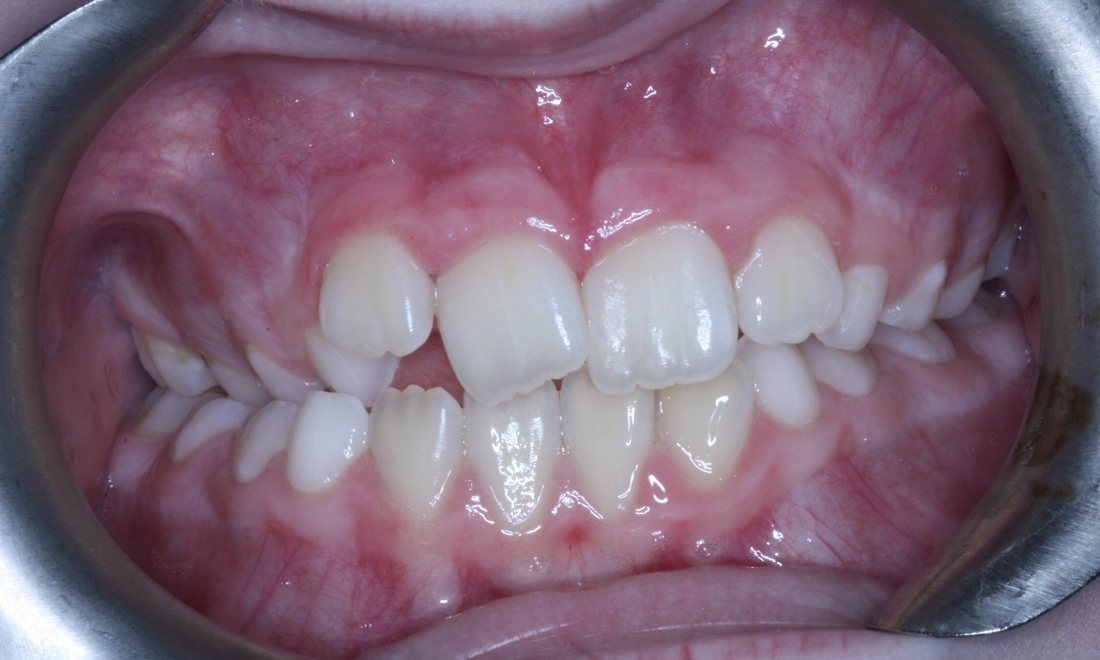

This patient had a narrow upper jaw which was expanded using an RME appliance and fixed appliances to align and level the arches. Total treatment time was 34 months